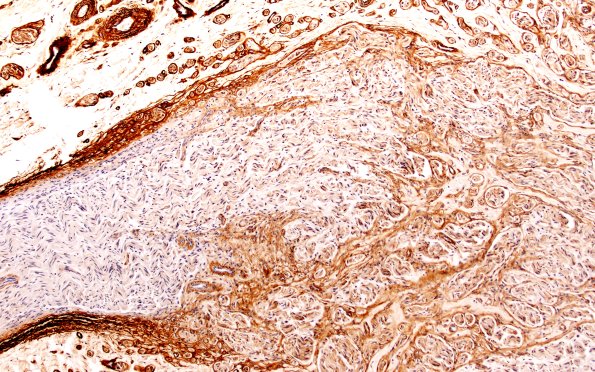

3B2 Neuroma (Case 3) Coll IV 10X

The emergence of mini-fascicles from the parent fascicles. (Coll IV IHC)